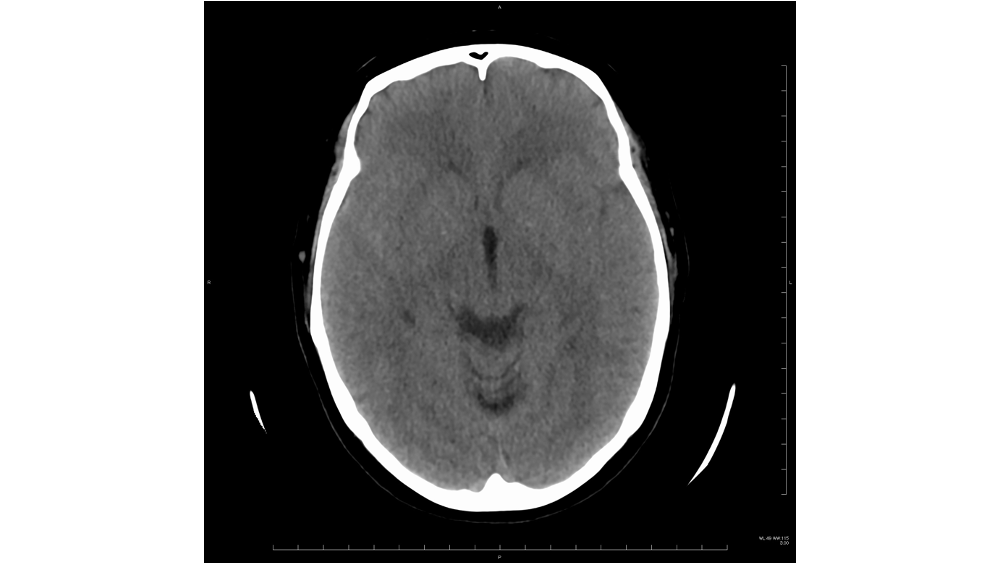

40歳代女性.テレビを見ていたときに突然の後頭部痛-後頚部痛を自覚し,当院救急外来を受診した.撮影されたCTを提示する.考えられる診断は何か?

• くも膜下出血

• 急性硬膜下出血

• 転移性脳腫瘍

• 異常なし